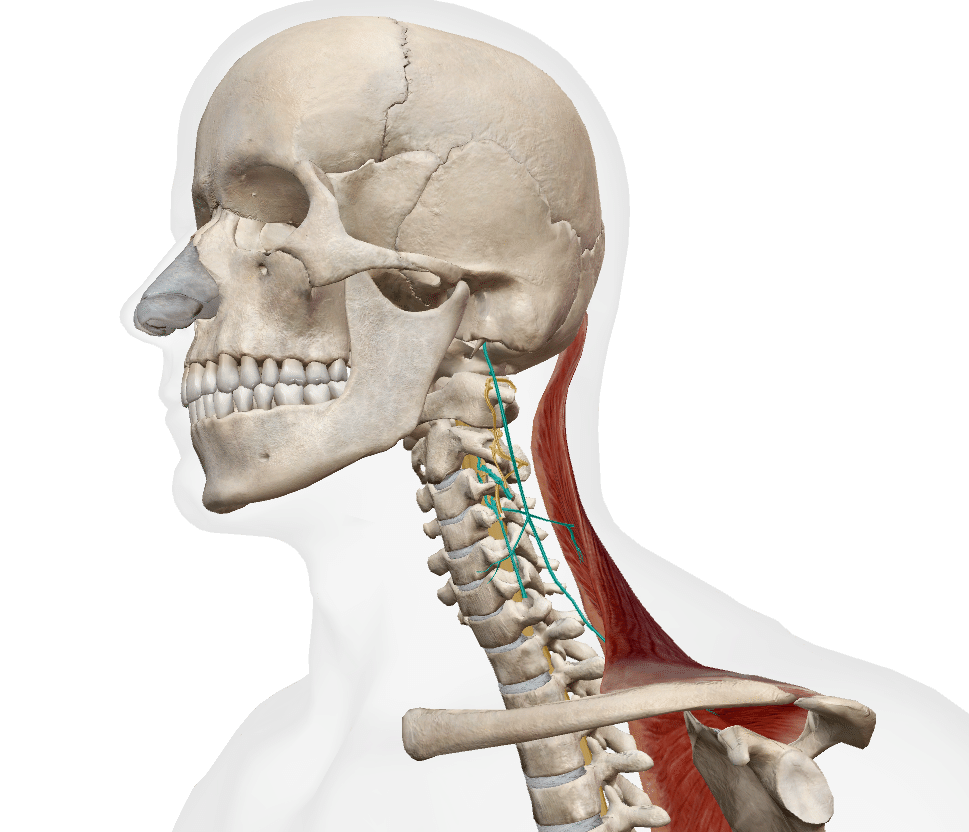

支配神経

副神経(CN11)

頚神経叢

(C3・C4)

支配神経である副神経は脳神経でもあり

僧帽筋と胸鎖乳突筋を支配します僧帽筋は、修道士がかぶる長頭巾(ながときん)に似ていることが由来である